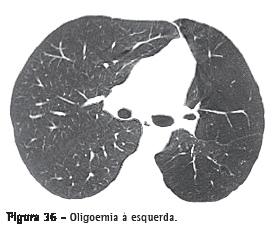

Oligoemia

Redução focal, regional ou generalizada do volume sanguíneo pulmonar. A oligoemia apresenta-se como uma diminuição do calibre e do número de vasos pulmonares em regiões específicas ou difusamente, indicando que o fluxo sanguíneo é menor que o habitual (Figura 36).(3,7)